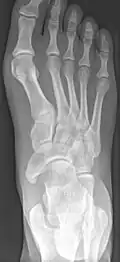

X-ray of the foot showing an accessory navicular bone

An accessory navicular bone is an accessory bone of the foot that occasionally develops abnormally in front of the ankle towards the inside of the foot. This bone may be present in approximately 2-14% of the general population and is usually asymptomatic.[1][2][3] When it is symptomatic, surgery may be necessary.